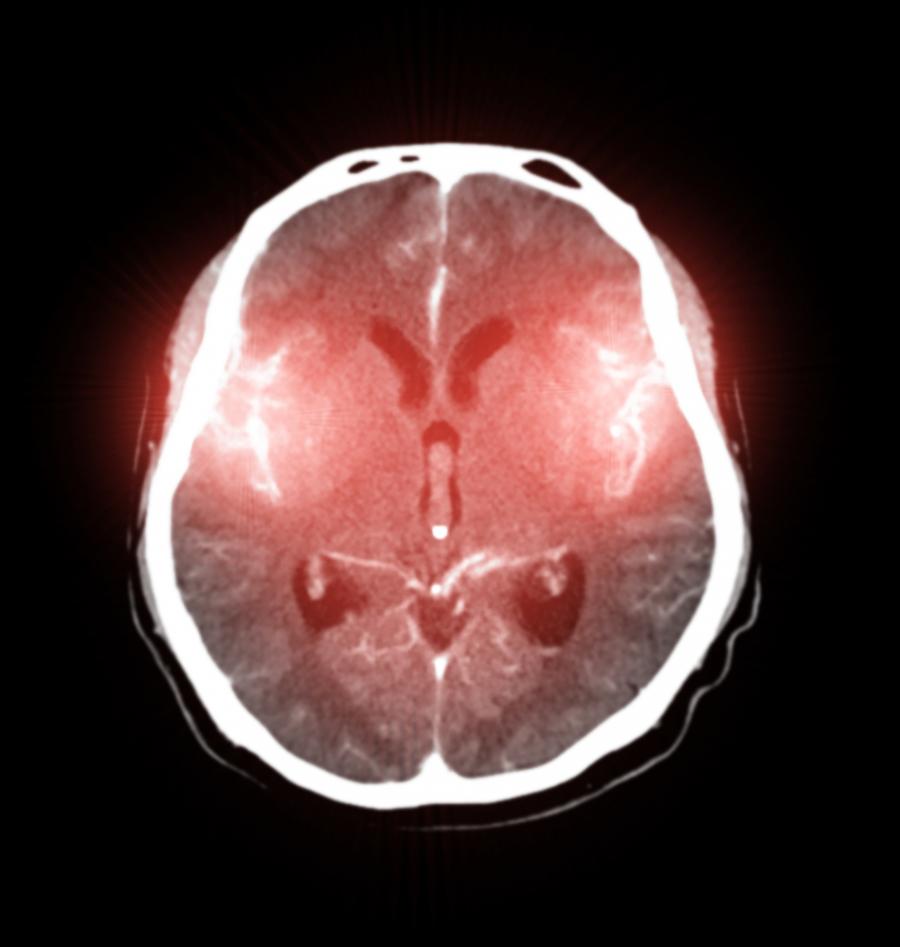

Сепсисът нанася значителни поражения във фронталната кора на мозъка, където се контролират движенията на тялото, речта и емоционалното изразяване. При драстично намаляване на нивата на кислород и притока на кръв в тази област на нервната система местната температура се повишава, което може да доведе до продължителни когнитивни проблеми, които са трудни за лечение, делириум и дори кома.